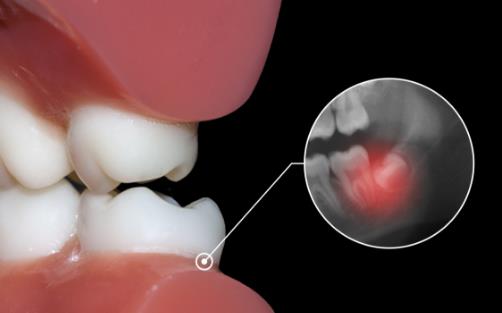

齲齒

位置不正的智齒與第二磨牙之間容易積存食物殘渣,而且不易清潔,一般數月可形成齲齒,直接破壞牙體組織。